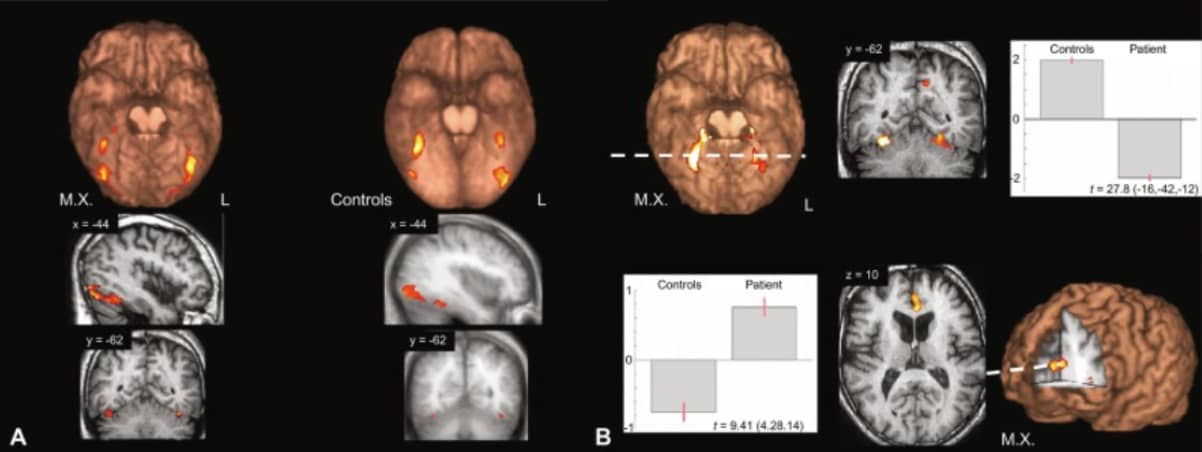

For example, in chapter 15 of the Handbook of Clinical Neurology, Rebecca Keogh and her co-authors discuss the case of MX.

A professional who used to visualize well suddenly found himself a-visual. He could no longer “enter” the novels he read, experience dreams visually, or visually recall faces of friends.

In his brain scans, researchers noted “hypoactivation of his anterior cingulate gyrus,” which means they were underperforming.